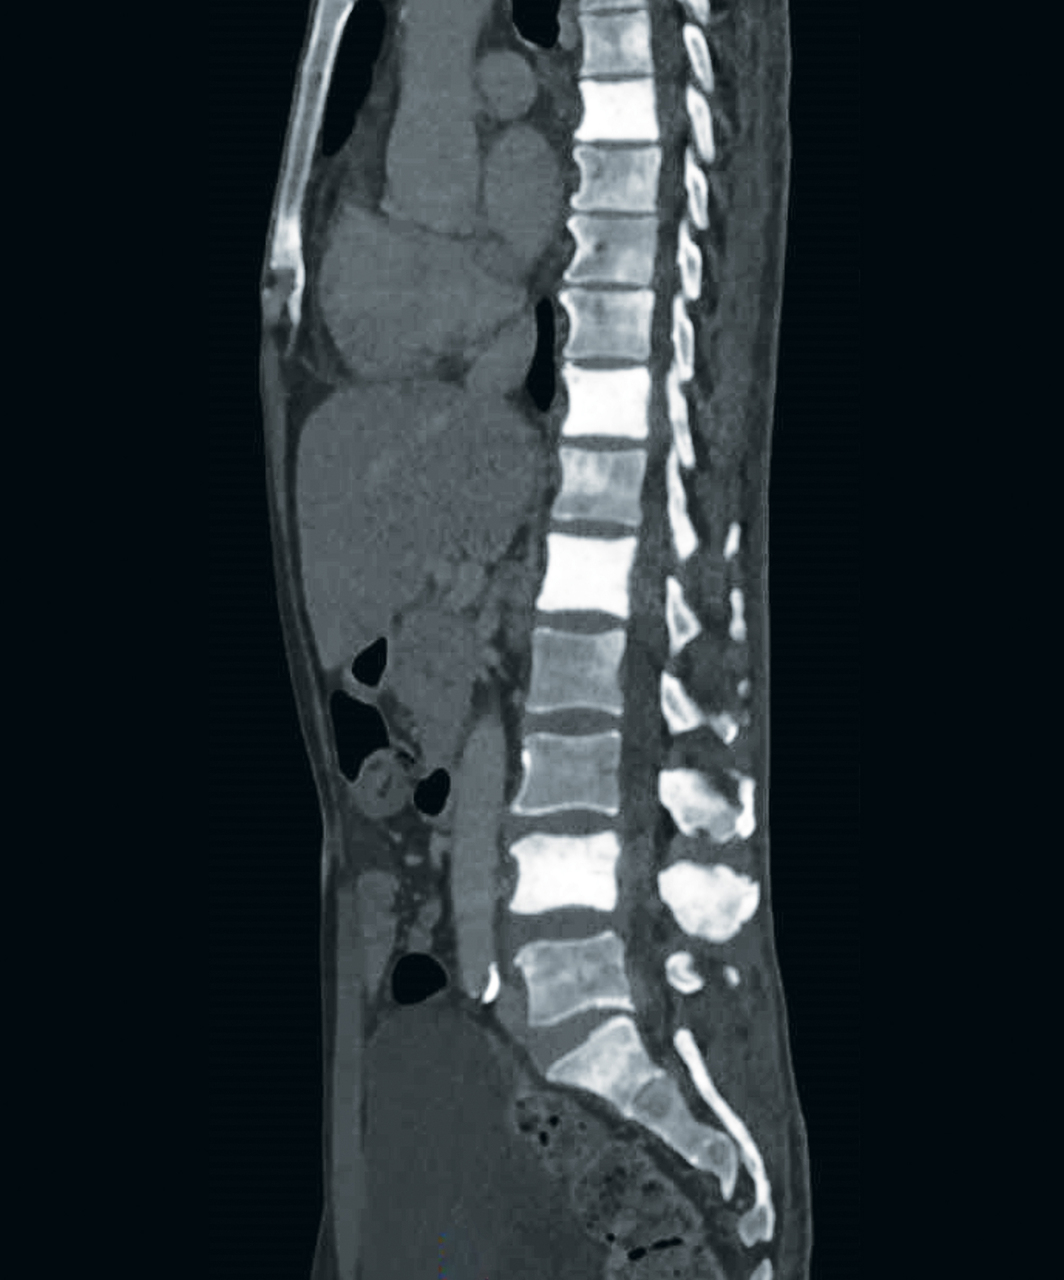

Un homme de 78 ans, originaire de Mauritanie, est hospitalisé pour douleurs diffuses et perte de poids de 25 kg en 3 mois.

La prostate est augmentée de volume et nodulaire. Le PSA est à 4138 µg /L. Les métastases osseuses de cancer de prostate peuvent être condensantes, comme celles du sein. Le patient a reçu un traitement par un analogue de la LH-RH et un inhibiteur de la synthèse des androgènes.

Les métastases osseuses de cancer de prostate peuvent être condensantes, comme celles du sein.